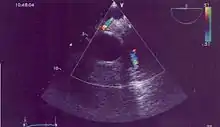

| Possible communication between left coronary artery and pulmonary artery in a 45-year-old woman with Bland-White-Garland syndrome. | |

Historically ALCAPA was diagnosed with conventional angiography. Today echocardiography is easily used. It can provide direct visualisation of the anomalous coronary artery and other associated structural abnormalities, and it can also assess myocardial function. The use of pulse and color-flow doppler can sometimes visualise reversal flow in the pulmonic artery. Other non-invasive methods used are computed tomography (CT) as well as magnetic resonance imaging (MRI) which enable a direct visualisation of the arteries as well as the myocardial viability.[3]